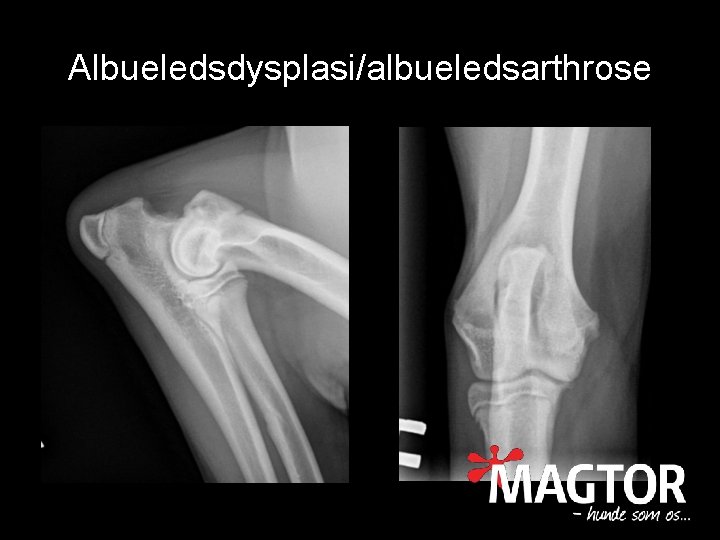

Albueledsdysplasi • Fællesbetegnelse – UAP – FCP – OCD • Symptomer ofte i ung alder • Ikke altid synligt på røntgen • Ofte operationskrævende

Albueledsdysplasi/albueledsarthrose

Albueledsarthrose